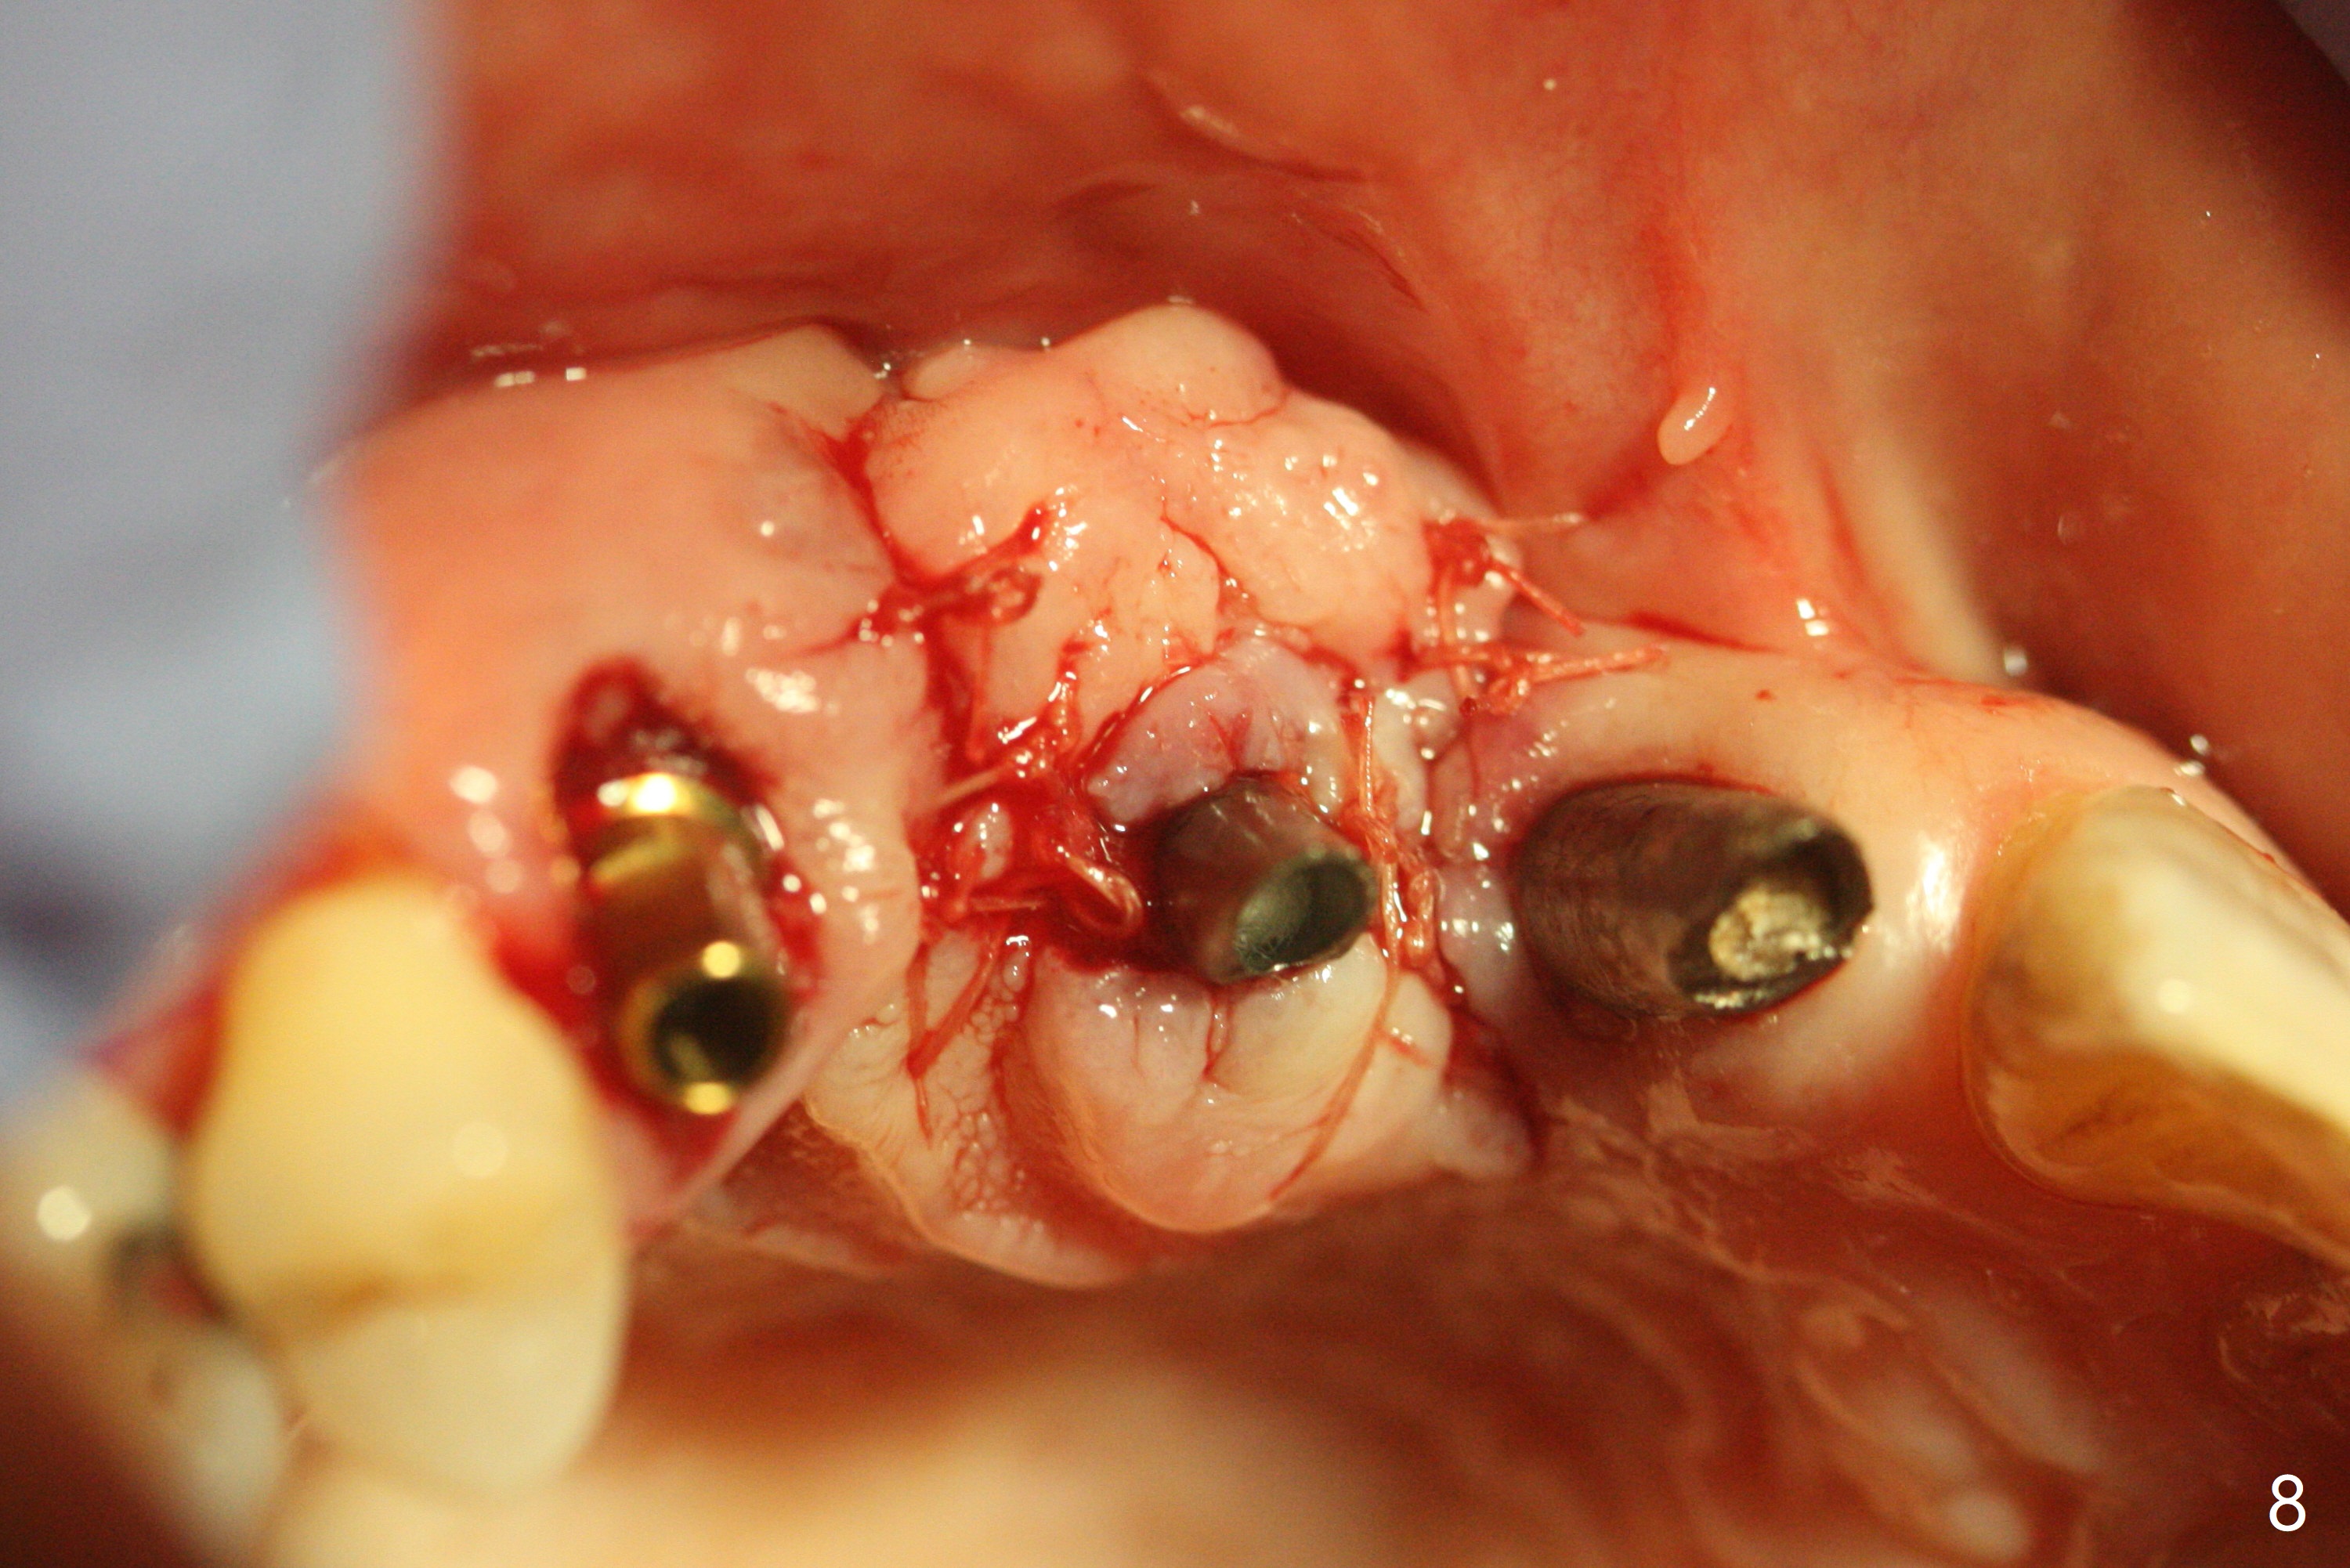

在6,7号牙位牙槽嵴切口,翻瓣,找不到上次放置的tenting screw,不过7号牙位骨质虽然低,够宽的,开始钻洞(图四),植入3.8乘8.5毫米植体,扭力足够(图五),近中舌侧暴露螺纹堆加骨粉(图五*),然后放置基台,再次在后者周围放置骨粉(图五至七),覆盖两张PRF膜后缝合(图八),最后在三个箭头周围放置牙周敷料。术后CT显示植体与tenting screws(图九,十箭头)有一定距离,但是5号牙植体颊侧根尖穿孔(图九 *)。如果植体不脱落,需做侧方切口植骨。术后七天7号植体腭侧肿胀(图十一 *),切开没有脓水,插入牙胶尖,它末端指向7号植体周围tenting screw。后者可能需要拔除,同时5号牙颊侧根尖植骨,但是为时太早,可能打搅骨粉生长。术后两周腭侧肿胀没有消失,但是不痛,继续观察。术后接近6个月,软组织正常(图十三),但是5,7植体周围没有骨质(图十四,五)。由于近中tenting screws周围软组织触痛(局麻不全情况下),螺钉取出(图十六,七(*)),而远中螺钉好像有帮助5植体螺纹骨粉撑起,所以留下(腭侧穿孔部分去除),最后放置粘性骨粉(图十八:*)和PRF膜(两张由7基台打孔固定)。